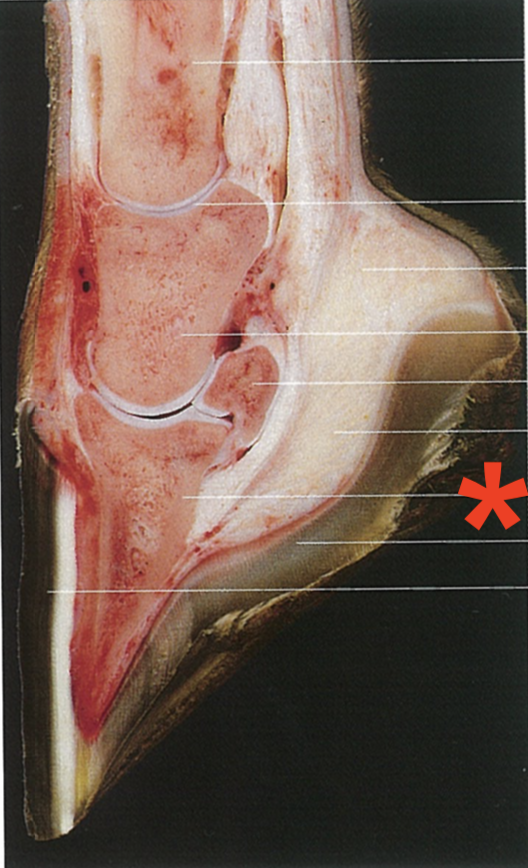

Which part of the hoof is shown?

The wall

Lateral palmar border

Dorsal part

Heel

Quarter

Sole margin

Distal phalanx

Sole horn

Wall horn

What has been removed from this hoof?

The hoof shoe